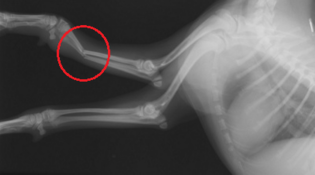

犬の骨折 の中でも 重症 レントゲン検査をして骨折を診断! 骨折の有無を確認するためには、骨の状態を確認できるレントゲンの検査が必要です。 レントゲン写真1枚あたり2,000~5,000円 ほどかかる病院が多いですが、骨折の状態によっては1枚だけで診断することができず、複数枚必要に当院を受診されるウサギの年齢は、犬同様に高齢化の傾向が認められます。 今回は高齢ウサギの前足の骨折がテーマです。 ライオンラビットのランちゃん(雌、9歳3か月、体重15kg)は前足を骨折したとのことで来院されました。 明らかに右前肢をかばっているため、レントゲンを撮りましたこれは、レントゲン写真を見ていただけたらわかるとおもいます。 この折れている指の骨を 「中手骨」 と言います。 6か月齢、体重4kgくらいのMIX犬のわんちゃんで、遊んでいるときに高い所から落ちてしまい、左前肢が跛行しているとのことで来院されました。

犬の中手骨の骨折について あおえ動物病院